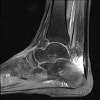

Lateral view X-ray에서 아킬레스 힘줄의 석회화, 뼈돌기, 발꿈치 뼈의 후상방 부위 돌출 등을 볼 수 있습니다.

MRI : 허글런드 변형(Haglund deformity)